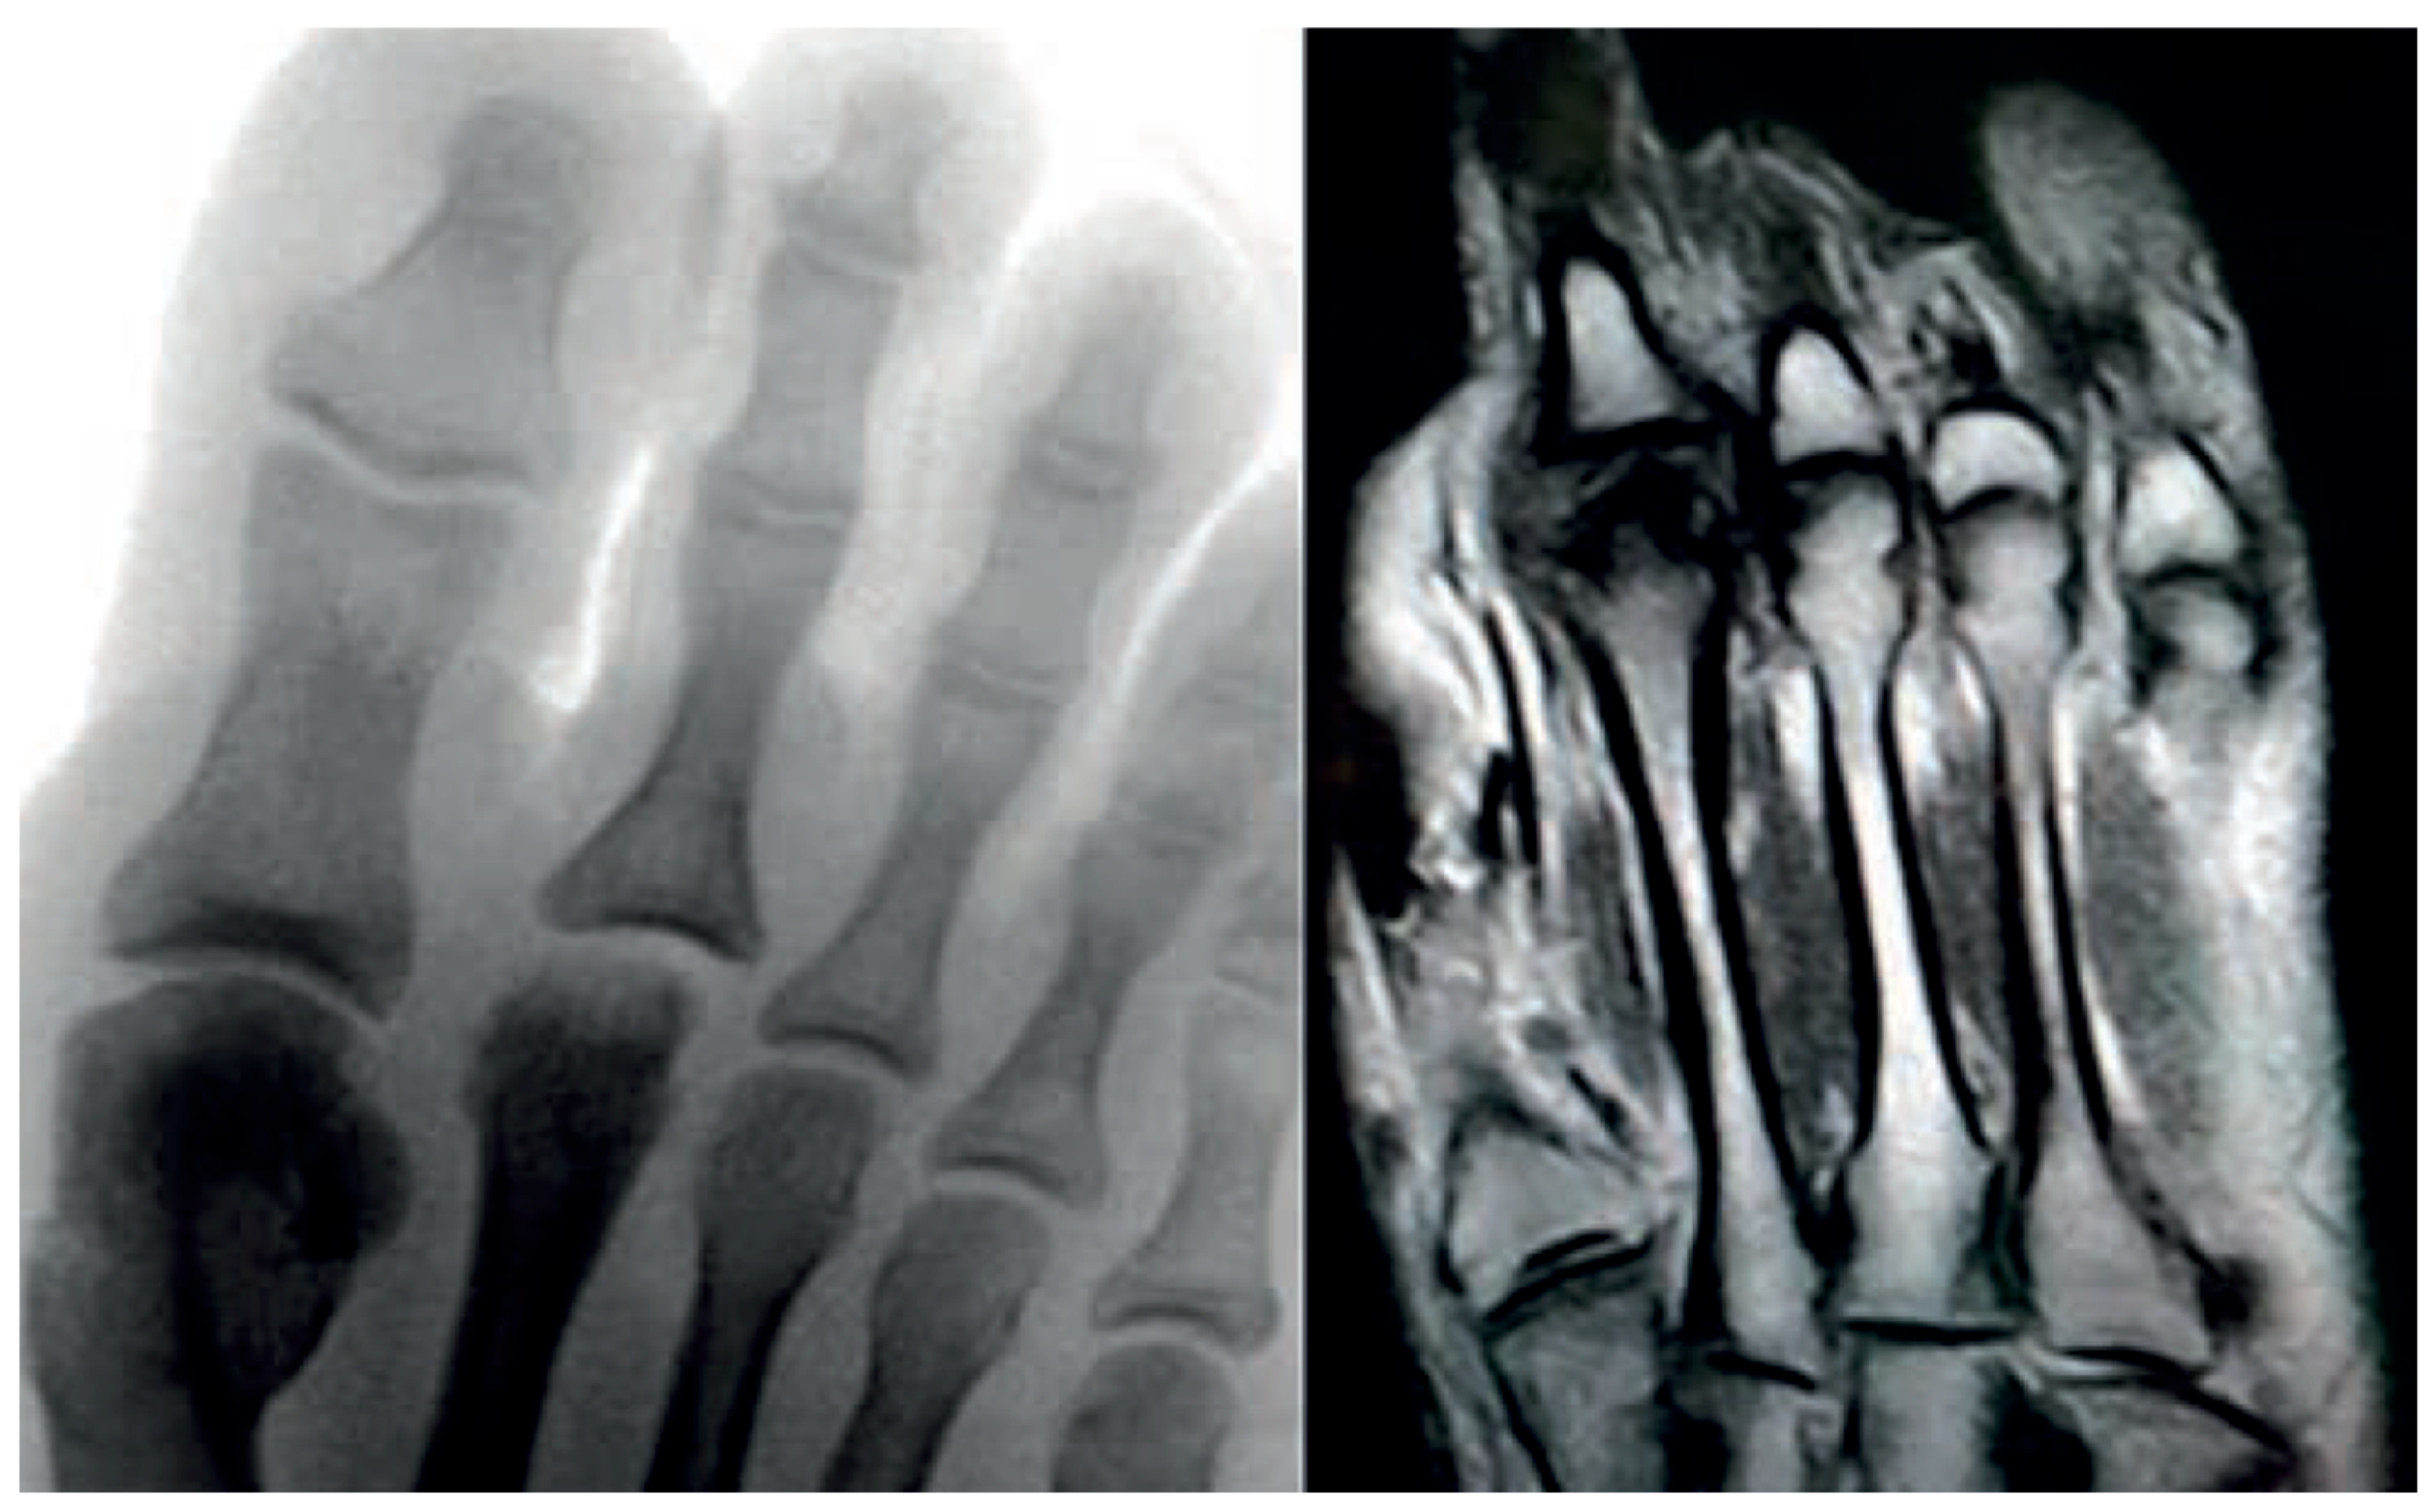

Figure 10.

Radiograph (left) and MRI (right) of a 17-year-old female patient showing necrotic changes and initial flattening of the second metatarsal head.

Figure 11.

Radiograph (left) and MRI (right) of a 15-year-old male patient with osteochondrosis of the third metatarsal head and early signs of deformation.

In the later stages, radiographs may reveal characteristic changes including subchondral sclerosis, fragmentation, and flattening of the affected metatarsal head (Figure 10 and Figure 11). In some cases, the presence of joint space narrowing or bony irregularities may also be observed. However, early changes, such as bone marrow edema or subtle cartilage damage, may not be visible on standard radiographs. MRI is particularly useful in the early stages of the disease, as it can detect bone marrow edema, which is a sign of active bone inflammation and necrosis, even before structural changes become apparent on radiographs (Figure 10, Figure 11 and Figure 12).